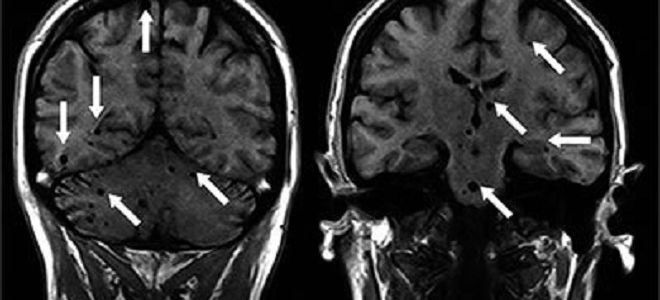

Установить присутствие паразитов в головном мозге человека можно при помощи компьютерной томографии и МРТ.

Диагностика нейроцистицеркоза

Установить диагноз больного нейроцистицеркозом довольно сложно. На первоначальных стадиях заболевание протекает бессимптомно. Для установления правильного диагноза используют рентген, МРТ и КТ. Свидетельствовать о наличии заболевания может повышенный уровень эозинофилов, положительный результат РСК.